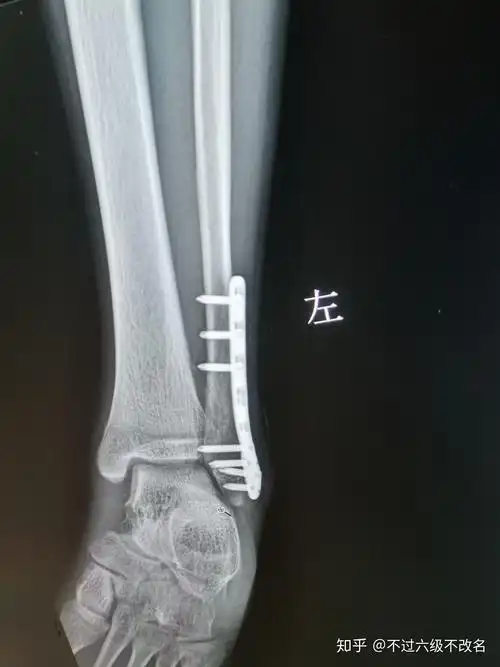

胫腓骨远端粉碎性骨折求手术方案 [病例帖]

62岁腓骨下段粉碎性骨折锁定钢板系统内固定手术一例

三例胫腓骨远端骨折

胫腓骨远端骨折